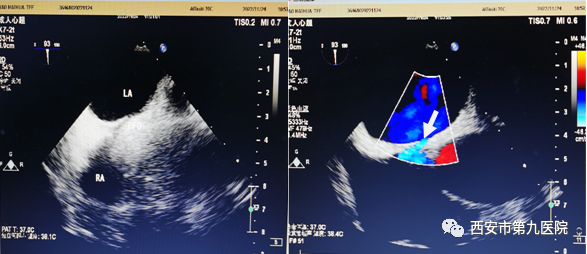

2023-02-27火眼金睛,一探究竟—经食道超声心动图

一、什么是经食道超声心动图? 经食道超声心动图(TEE)——是把超声探头微型化成胃镜一样的细管道伸入食道里面,从心脏后面直接探查测量心脏结构和血流有无异常。 ... -